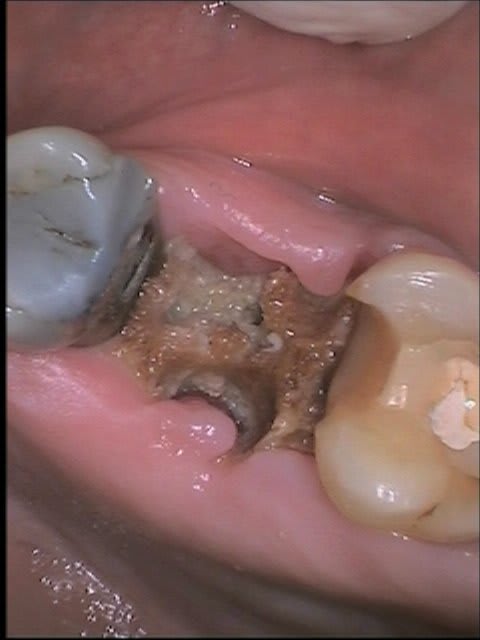

C'est l'os qu'on voit en marron? Parce que ca sent le séquestre dans ce cas

C'est effectivement de l'os

tu fais un curetage pour relancer le processus de cicatrisation et supprimer le sequestre

c'est simple, tu anesthésies (sans vaso), tu décolles en pleine épaisseur en lingual et en vestibulaire et tu vires ce qui a un vilain aspect. tu grattes j'usqu'a ce qu'il y ait un afflue sanguin issu de l'os. et tu refermes bien.

si possible anapath car ça sent pas bon ce truc.

Commence par une bonne anamnèse.

Radiothérapie, biphosphonates, gros diabétique qui ne le sait pas.

Evolution de la lésion, pourquoi il a mis 4 mois à s´inquiéter.

Et si aucune contre-indication antibiotique gratter tout ce qui ne saigne pas et bien suturer.

Une fois que tu auras bien tout nettoyé, je te propose de mettre un eugenate et de le changer 2 fois par semaine, ce qui évite à ton épithélium de cicatrisation d'être grillé par la cigarette.

Inconveignant il aura un cratère a cet endroit un certain temps.

Avantage cela marche très bien.

m'étonnerait pas si sous le séquestre c'était déjà ré épithélialisé. Tu vas te retrouver avec un gouffre mais quasi sain au fond. Mais effectivement d'abord voir si diabète, bisphosphonates ou XGeva, même si çà ne change rien, de toute façon faudra nettoyer, toi ou un spé.

Sinon, je pense aussi que c'est ré-épithélialisé en dessous, au vu de la photo.